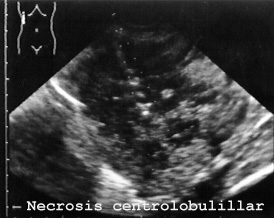

El hígado en la necrosis centrolobulillar hepática presenta características propias en la ecografía postmortem con zonas hipoecoicas (negras) y otras hiperecoicas (brillantes) (Fig 7).

07NECROX.JPG (24438 bytes)

Fig 7

Esta imagen corresponde a necrosis centrolobulillar como demuestra el estudio histológico (FIG 8).

En este caso la autopsia no diagnosticó la necrosis centrolobulillar del hígado que afectaba al 85% del lóbulo derecho, al (15%) del izquierdo y 100% del lóbulo cuadrado según el barrido ecográfico realizado. La paciente era una niña de 19 meses de edad que había sufrido una aspiración alimenticia. Fue tratada durante un mes con ventilación asistida. Falleció finalmente con distress respiratorio tipo adulto e insuficiencia hepática demostrada desde una semana antes de la muerte. La autopsia no tomó material de las zonas afectadas, probablemente porque no fuera muy evidente a ojo desnudo y no diagnosticó lesión importante en el hígado (Fig 9).